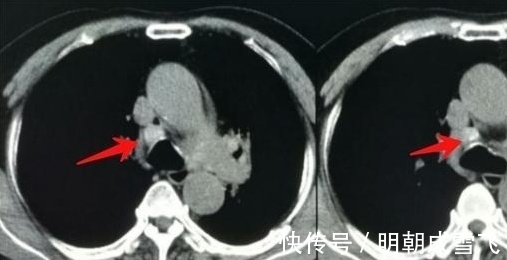

文章插图

这是一例小细胞肺癌广泛转移,5年后复查:

治疗效果这么好的病例,目前还只是一小部分。